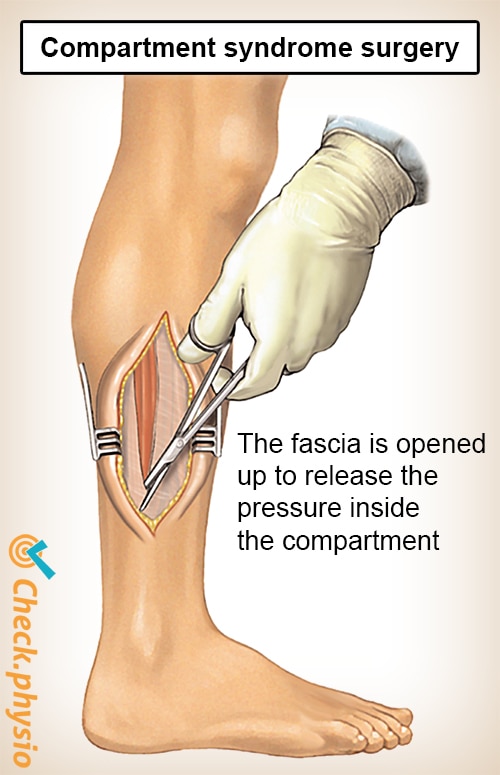

Acute Compartment Syndrome ACS of the lower leg is a time sensitive limb threatening surgical emergency Late findings of ACS can lead to limb amputation contractures paralysis multi organ failure and death

Acute Compartment Syndrome ACS of the lower leg is a time sensitive limb threatening surgical emergency Late findings of ACS can lead to limb amputation contractures paralysis multi organ failure and death

Acute Compartment Syndrome ACS of the lower leg is a time sensitive limb threatening surgical emergency Late findings of ACS can lead to limb amputation contractures paralysis multi organ failure and death

A Guide Through Fasciotomy Surgery

Compartment Syndrome Acute Chronic Anatomy And Operation

Compartment Syndrome Acute Chronic Anatomy And Operation